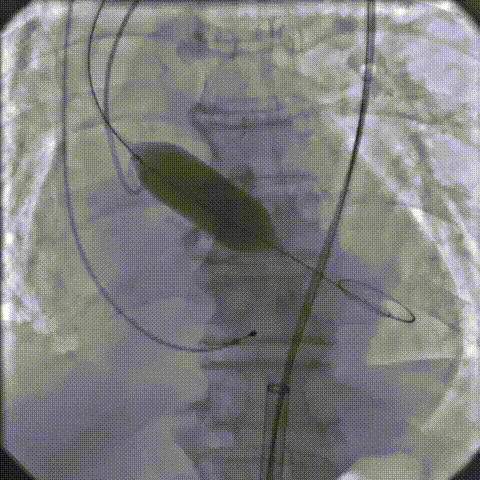

18mm球囊预扩

零位定位逐步释放至工作位,多角度评估位置良好

缓慢脱钩至完全释放,最终植入位置理想